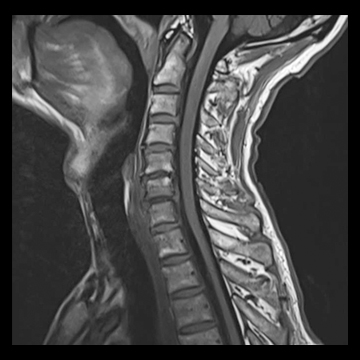

頚椎

T1 TSE, 384 matrix,

T2 TSE, 384 matrix,

T1 TIRM, 320 matrix,

全脊椎

T1 TSE, 448 matrix

T2 STIR, 384 matrix,